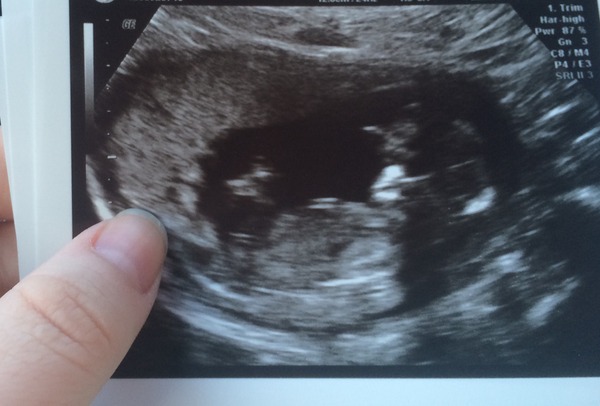

Hi girls! Back from my scan! I am 12+5 and have a wriggly little baby! It was jumping on screen and waving and sucking it's thumb! So so special :)

I've attached a pic!

Lovely scan Natalie! How exciting!!

Congrats natalie lovely scan pic!